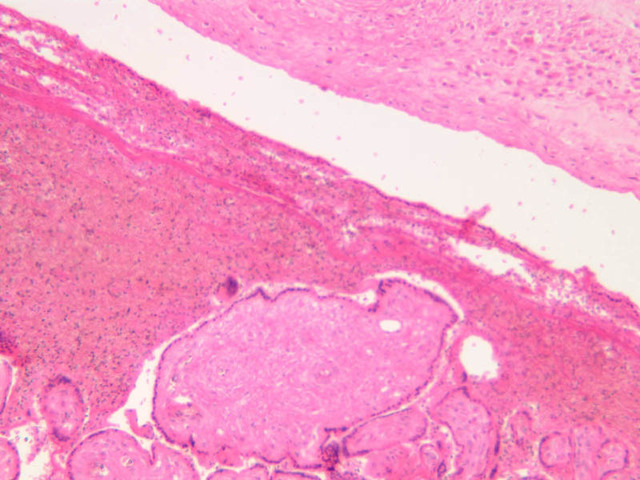

Uterine Cervix

The endometrium of the cervical canal does not slough during the menstrual phase. The glands in this region are relatively large and extensively branched. They are lined by a tall simple columnar epithelium very active in the secretion of mucus. Occasionally these glands become blocked forming Nabothian cysts. The transition of the epithelium of the cervix to that of the vagina is abrupt and is in the region of the external os. At this point, the cervical simple columnar is replaced by the vaginal stratified squamous epithelium (slide B-98 [2.5x-labeled, 10x, 20x, 40x] [2.5x, 10x, 20x, 40x]). This is an area which is commonly inflamed as well as a primary location of cervical cancer.

Vagina

The mucosa of the vaginal wall is lined by non-keratinized stratified squamous epithelium which rests on a lamina propria. The epithelium is indented from beneath by connective tissue papillae. Occasionally aggregations of lymphocytes may be seen within the lamina propria (slide B-98 [2.5x-labeled, 10x, 20x, 40x] [2.5x, 10x, 20x, 40x] [1x, 1x, 1x, 1x, 1x]). The muscularis is said to consist of a poorly defined inner circular and outer longitudinal layer of smooth muscle. An adventitia of fibrous tissue forms the outer most layer of the vaginal wall. Although there is a rather rich vascular plexus in the lamina propria, no glands are present at any location in the vaginal wall.